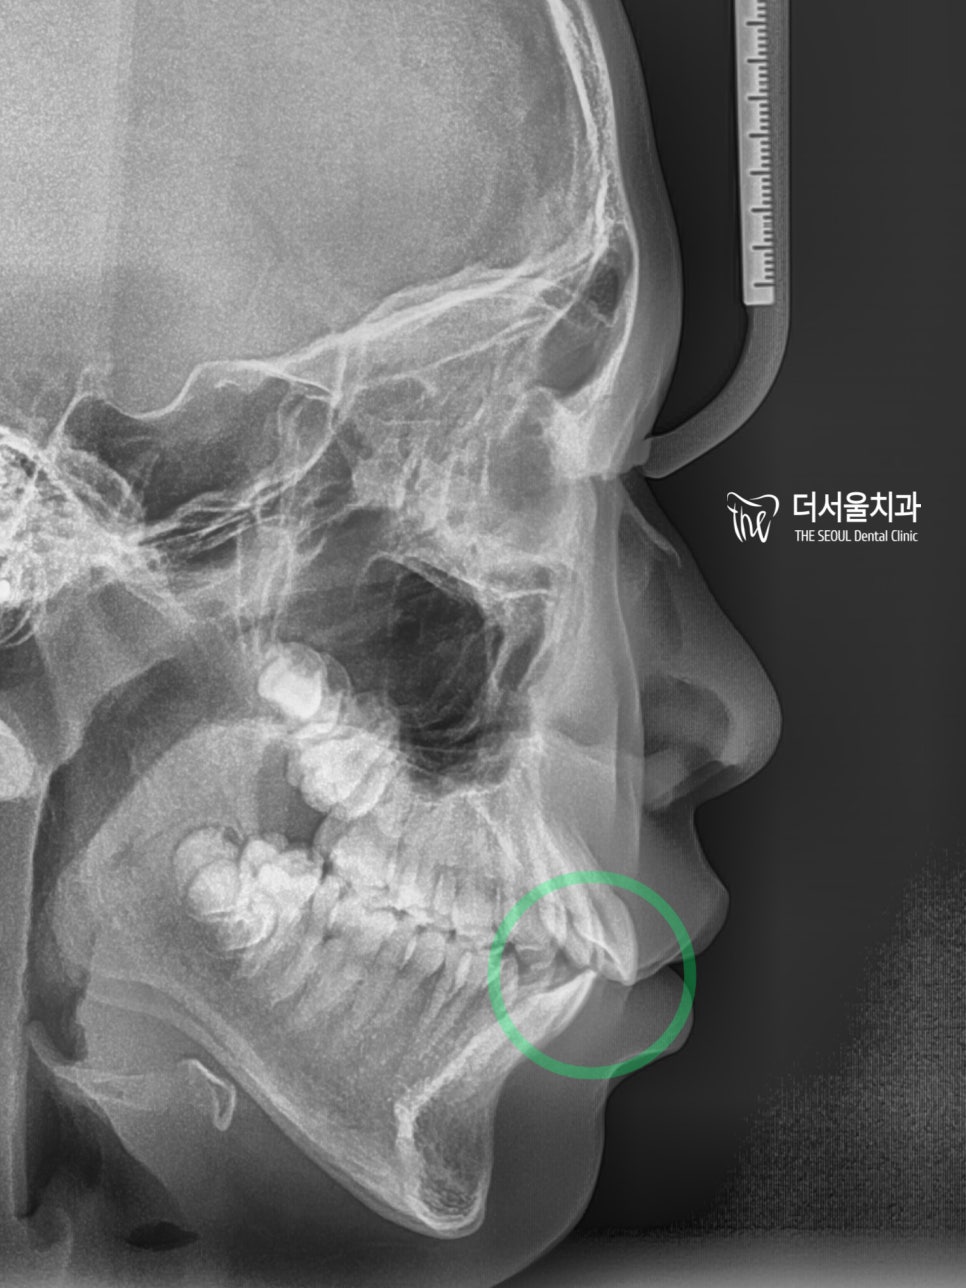

측면 세팔로 사진에서 볼 수 있듯이

돌출감이 꽤 느껴지고 있었습니다.